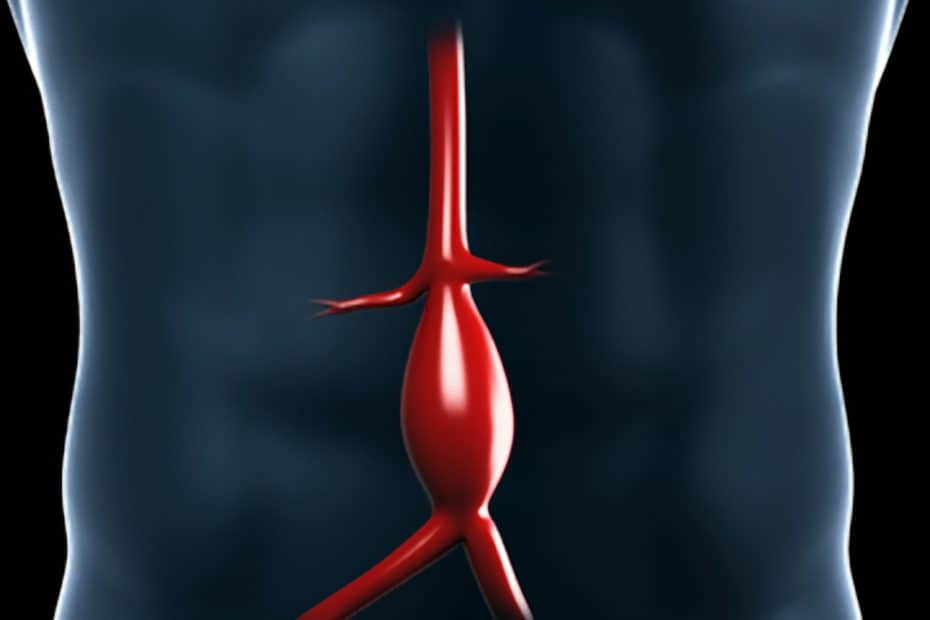

Un aneurisma aórtico abdominal es un agrandamiento de la parte baja de la aorta que se extiende a.

aneurisma de la aorta abdominal La aorta va desde el corazón hasta el. Recibe sangre con gran contenido en oxígeno. Cirugía vascularrupturas de aneurisma de la aorta abdominal: La cirugía de reparación abierta de aneurisma aórtico abdominal (aaa) se realiza para arreglar una parte dilatada de la aorta. Si tienes un aneurisma de la aorta abdominal en expansión, podrías notar lo siguiente: La incidencia de aaai en. En este artículo examen físico pruebas de detección y de diagnóstico ¿quiénes deben someterse a un examen de detección de aneurisma de aorta torácica? Los aneurismas aórticos aneurismas aórticos la aorta, que mide alrededor de 2,5 cm de calibre o diámetro, es la arteria más grande del cuerpo.

Aneurisma aórtico abdominal localización y apariencia. 2022

Source: www.deperu.com